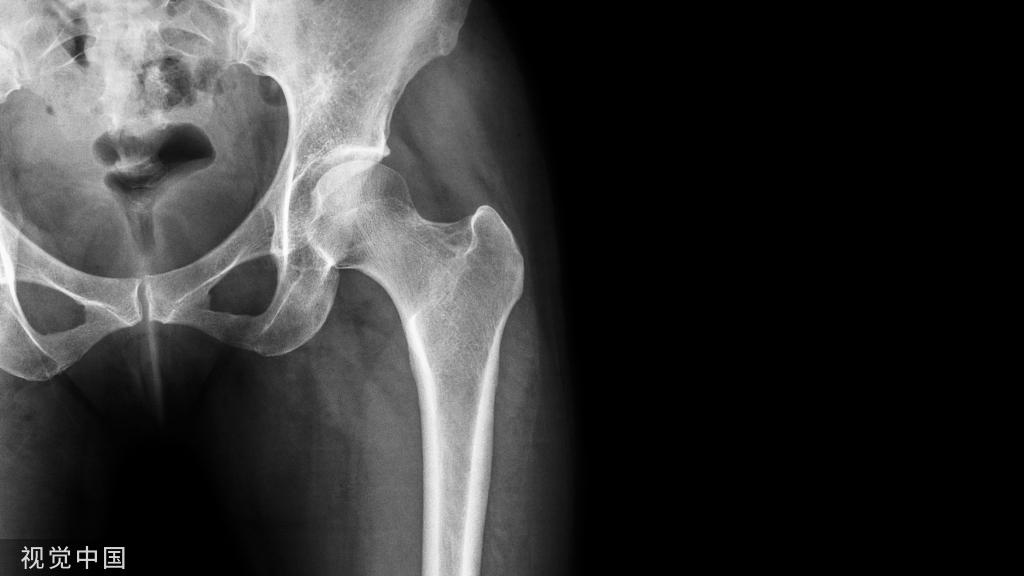

创伤后的下尺桡关节炎

桡尺远端骨折 (DRF) 后远端桡尺关节 (DRUJ) 关节炎 经常容易忽视 桡尺远端关节 (DRUJ) 的乙状切迹受累在桡骨远端关节内骨折 (DRF) 中高达 80% Colles 骨折中 DRUJ 骨关节炎的患病率为 5%。

首先我们需要注意的就是 在治疗桡骨远端时,不要忘了看一下尺桡关节的匹配程度,避免漏诊